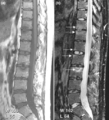

I thought that this would be helpful to those that are looking for answers or those that would like to see what radiographic evidence looks like and how it is defined... (a) T1-weighted and (b) short tau inversion recovery (STIR) magnetic resonance images of lumbar and lower thoracic spine in psoriatic arthritis. Signs of active inflammation are seen at several levels (arrows). In particular, anterior spondylitis is seen at level L1/L2 and an inflammatory Andersson lesion at the upper vertebral endplate of L3. The fourth, fifth and sixth vertebra contains certain peculiarities, which are detailed below. Radiology shows the appearance of "fluffy, new" bone or bridging/fusion.